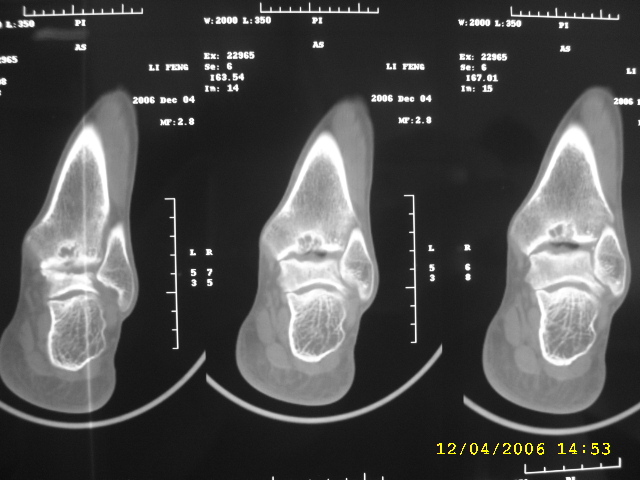

男,44,双踝关节肿胀,疼痛,活动受限2月余。无外伤史。

双侧距骨及胫骨都有骨质破坏,还很对称,最好追问一下病史,看这人有没有痛风。

双侧距骨可见多发囊变区,边缘硬化内可见更高密度影,考虑1双侧踝关节结核2退行性骨关节病

双侧距骨关节面下可见多发囊变区,边缘硬化内可见更高密度影。考虑:双踝剥脱性骨软骨炎。

双侧距骨及胫骨都有骨质破坏,边缘硬化内可见更高密度影,双侧对称性发病,踝关节及跟距关节内低密度影(气体影?),双侧对称发病基本可以排除关节结核及化脓性关节炎,痛风性关节炎以第1跖趾关节为典型发病部位,临床症状间歇性发作,受累关节非对称性肿胀与本例不符,首先考虑退行性骨关节病,请结合抗\"o\"及类风湿因子检查排除风湿性关节炎。

跟进!关节间隙明显变窄,诸相对骨性关节面增生、硬化,内见多发囊变,考虑增生性骨关节病!

双侧距骨及胫骨近关节面都有骨质破坏,边缘硬化,唇样变,内可见囊状低密度影,双侧对称性发病,首先考虑退行性骨关节病。